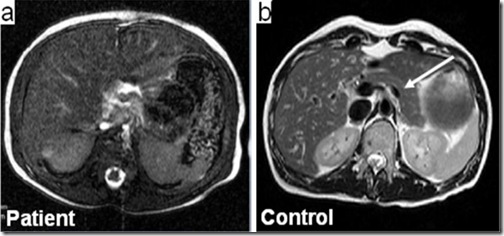

Al secuenciar sólo los genes codificantes (exoma) de estos pacientes, los investigadores detectaron mutaciones del gen gata6 en 15 de ellos (~57%), las cuales no fueron encontradas en los padres, confirmándose así que se trata de mutaciones de novo. Además se observó que 14 de los 15 afectados por esta mutación presentaban defectos cardiacos congénitos y en algunos casos se observó anomalías en el tracto biliar y digestivo, y problemas neurológicos, lo que indicaría que el gen podría estar involucrado en el desarrollo de diferentes órganos.